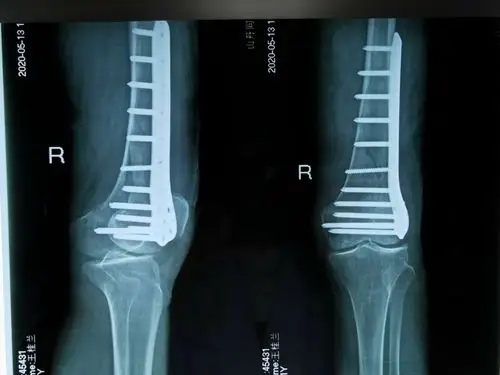

右股骨髁间粉碎性骨折

股骨髁部骨折术后